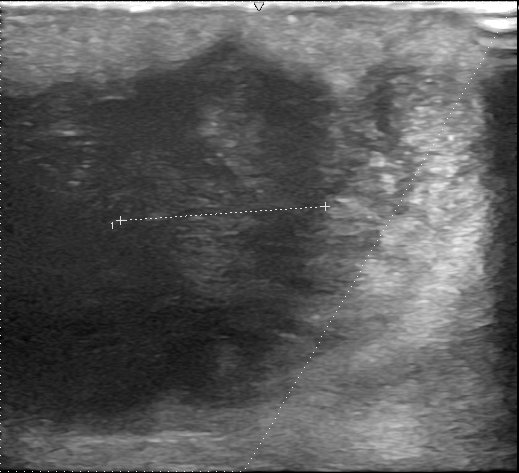

2回目の再発術前

小切開による切除手術を行い、半年後の再診時には5mmの再発が認められたため、追加切除を行いました。肉眼的には完全切除されていましたが、その半年後の再検査で再び再発が認められたため、再度追加切除を実施しました。病理検査の結果、粉瘤であり悪性腫瘍ではないことが確認されました。